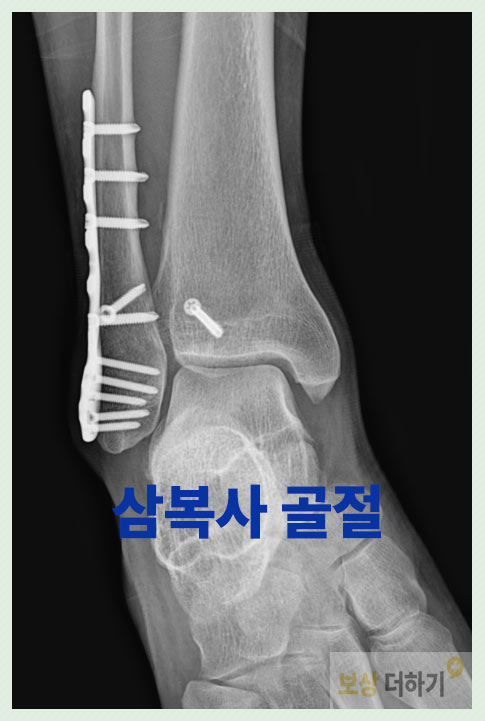

삼복사 골절은 양쪽 복숭아뼈와 뒤쪽의 후과까지 3군데가 모두 손상된 것입니다. 발목 골절 중에서도 비교적 심각한 부상이기 때문에 수술 후에도 후유증이 남을 확률이 높습니다. · 뼈의 불유합 · 발목 관절의 운동 범위 제한 · 외상성 발목 관절염 · 기타 이러한 후유증이 남게 되면 후유장해 보상이 가능하니 꼭 검토해 보셔야 합니다.

진단명 삼복사 골절, 발목, 폐쇄성 s82830

심각한 발목 손상이었기에, 골절 부위에 금속을 삽입하여 고정하는 관혈적 정복 및 내고정술이 시행되었습니다.